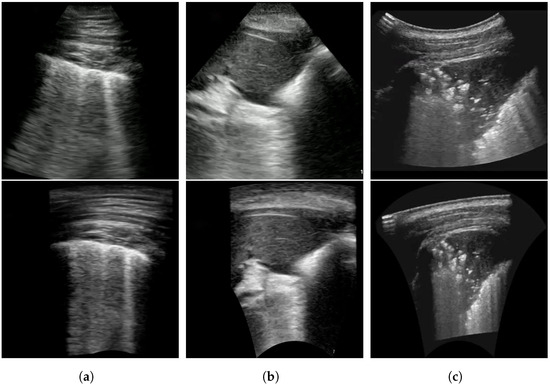

Furthermore, during training, we can transform the POCUS images obtained via both linear and convex probes using random projective transforms as a data augmentation. This process enhances their visual resemblance to POCUS images captured by a convex probe, allowing the deep neural network to more effectively harness this additional data source. An example result of this POCUS augmentation is shown in Figure 2b,e, with Figure 2a,d as the original images respectively. In comparison to the original, Figure 2b can be seen to have slightly increased the slant of the viewing window, while Figure 2a was transformed into a more conical shape, which is more similar to the appearance of convex probe results.

This transformation requires significantly more computing time compared to using projective transforms, as it requires estimating the transformation for multiple sections of the image. An insufficient density of points also results in artifacts between each section of the image. With a sufficient density of points, however, the results of this transformation look significantly more realistic compared to the simpler projective transform and can handle a greater change in slope with few distortions. Examples of both transforms can be seen in Figure 2.

Figure 2. Proposed image transformations on convex ultrasound images (b,c) and linear ultrasound images (e,f). (b,e) is generated using projective transform, while (c,e) is generated using piecewise affine transform. The original images prior to transformations are shown in (a,d).